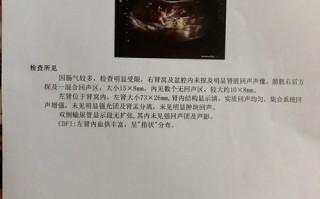

(图片来源网络,侵删)- B超(超声):是孕期和新生儿期首选、无辐射的检查方法,可以发现大部分较大的囊肿。

- 磁共振成像:是评估蛛网膜囊肿的“金标准”,它能非常清晰地显示囊肿的大小、位置、形态,以及与周围脑组织、血管和神经的关系,有助于与其他类型的囊肿(如表皮样囊肿)相鉴别。